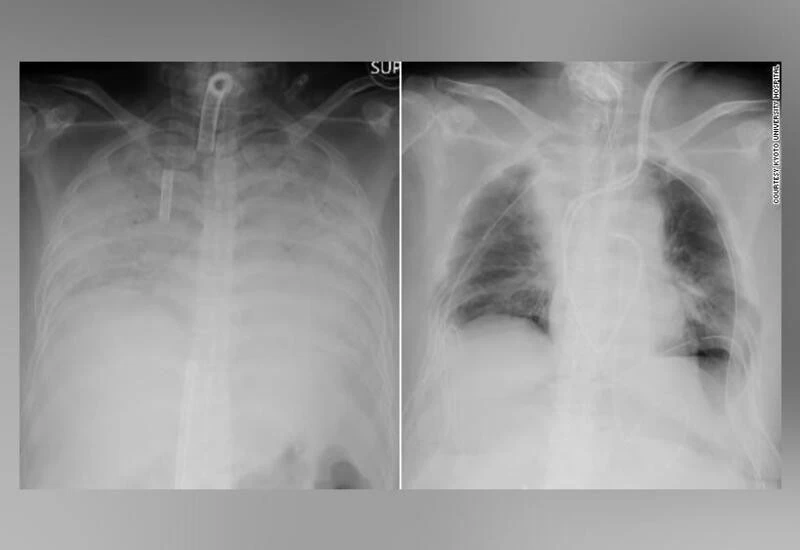

It was reported that the woman had no pre-existing medical conditions but her respiratory function deteriorated rapidly after she was infected with the coronavirus at the end of last year. She developed pneumonia and that caused both her lungs to harden and shrink, destroying most of their functionality.

According to Kyodo News, The operation, which took around 11 hours to perform, transplanted part of healthy lungs from the patient's husband and son to replace her failing lungs. Both donors are in stable condition, and the patient, who is currently in intensive care, is expected to be discharged in two months if all goes well, the hospital said.